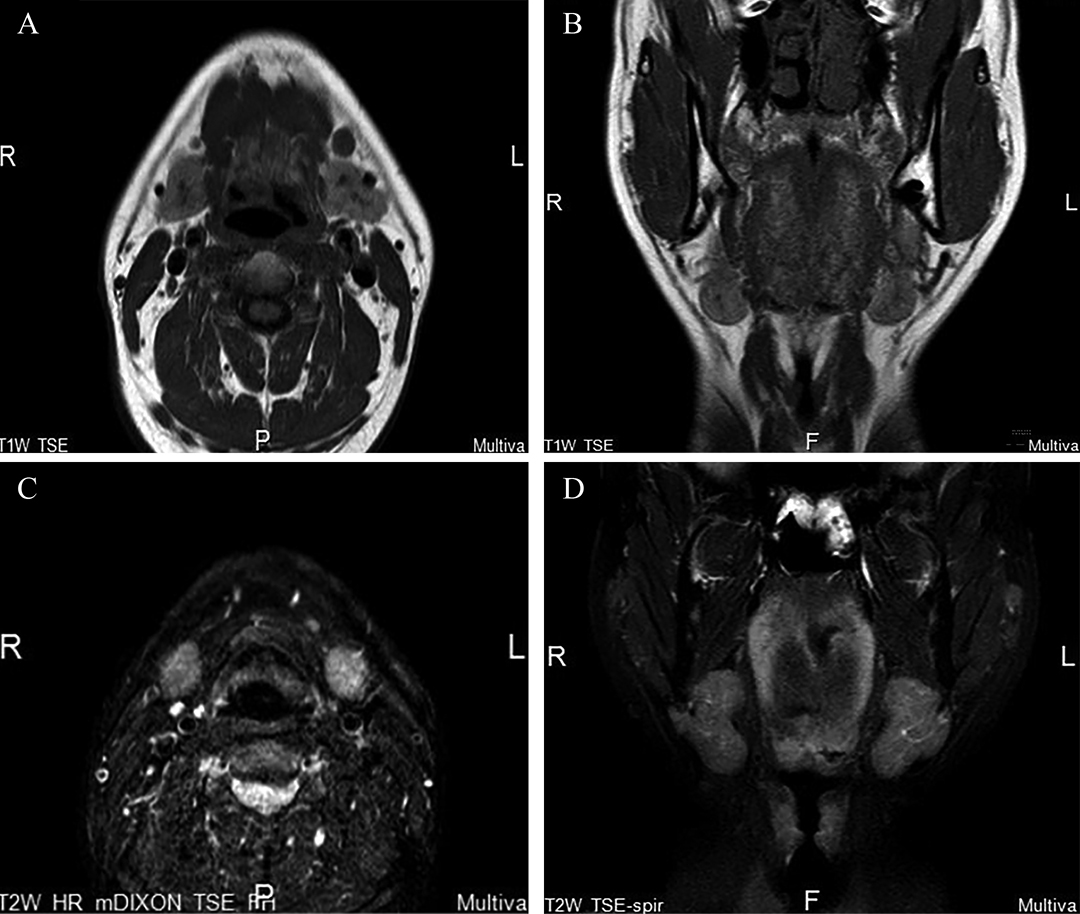

• 图4 潜突型舌下腺囊肿术后复发MRI A.颈部MRI横断面(T1WI期);B.颈部MRI冠状位(T1WI期);C.颈部MRI横断面(T2WI期);D.颈部MRI冠状位(T2WI期)。